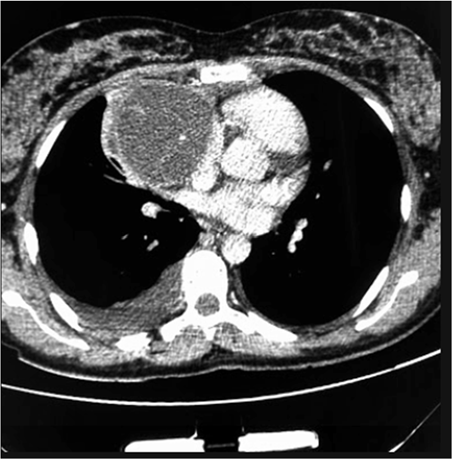

Um paciente de 17 anos de idade revela idas frequentes à emergência por causa de tosse e dispneia. Em exame de imagem investigatório, identificou-se, na tomografia computadorizada de tórax (TCT), uma massa mediastinal anterior bem definida, com densidade de partes moles, medindo cerca de 17 cm x 11 cm x 10 cm, conforme representado na imagem a seguir. A lesão não invadia estruturas adjacentes, e não foram encontradas outras alterações nas tomografias de tórax, de crânio e de abdome. Foi realizada uma biópsia pré-operatória guiada por TCT, cujo diagnóstico foi compatível com teratoma de mediastino.

Considerando esse caso clínico, a imagem apresentada e os conhecimentos médicos correlatos, julgue os itens a seguir.

O quadro clínico apresenta um tumor de mediastino anterior. O teratoma cístico maduro trata-se da neoplasia mais comum das células germinativas do mediastino.